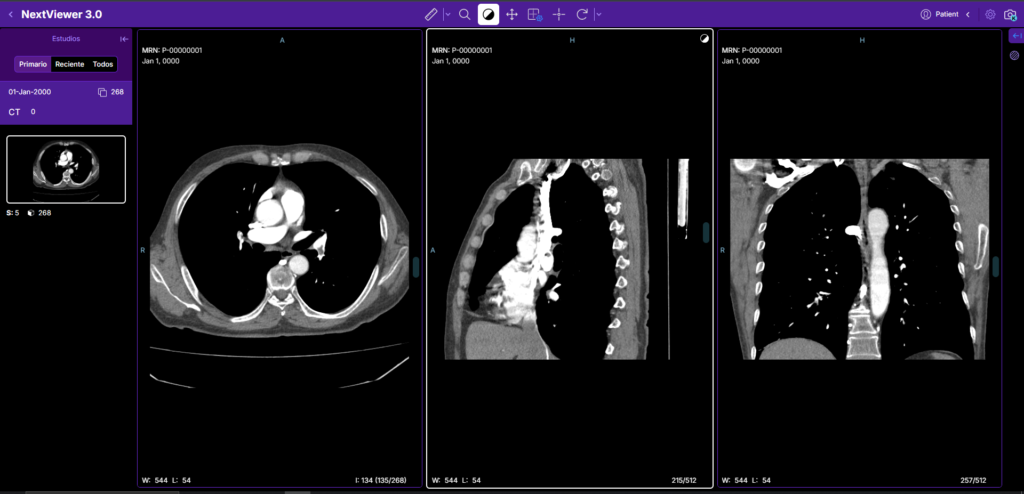

Gestión de imágenes clave

El radiólogo puede seleccionar y marcar imágenes clave del estudio directamente desde el generador, vinculándolas al informe para resaltar los hallazgos más relevantes:

– Señalar cortes o frames diagnósticos críticos dentro del set DICOM

– Contextualizar visualmente el informe sin que el receptor necesite revisar todo el estudio

– Agilizar la revisión por parte del médico solicitante